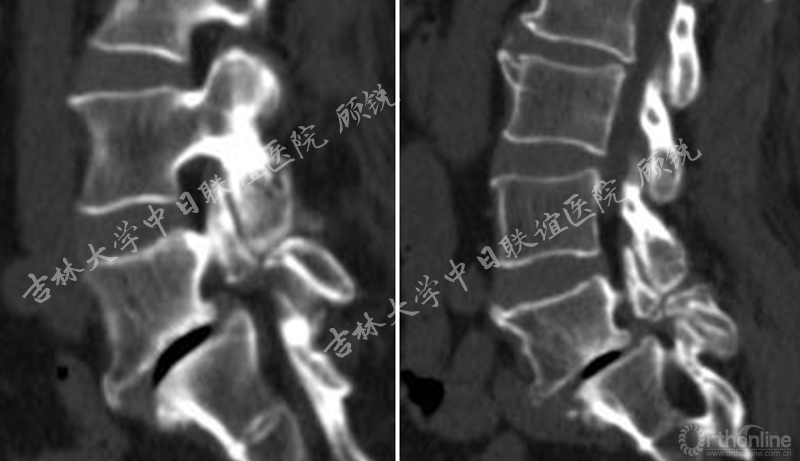

腰椎增强MRI示:

占位组织强化明显为实质病变,依据瘤体与硬膜间呈锐角;T1W1:等信号;T2W1:混杂高信号STIR:环状增强,Non-enhancement area(+)。经科内会诊该患者的诊断为:峡部裂型腰椎滑脱(L5 Ⅱ度)、腰椎管内占位性病变(神经鞘瘤?)。Ozawa H, Aizawa T, Kanno H.Epidemiology of surgically treated primary spinal cord tumors in Miyagi, Japan.Neuroepidemiology. 2013;41(3-4):156-60

责任病变是峡部裂型腰椎滑脱(L5 II度)。诊断依据:临床思维一元论原则(Unitary theory);患者左侧L5神经根的症状与CT显示左侧L5S1椎间孔狭窄对应;椎管内瘤体主要位于右侧。